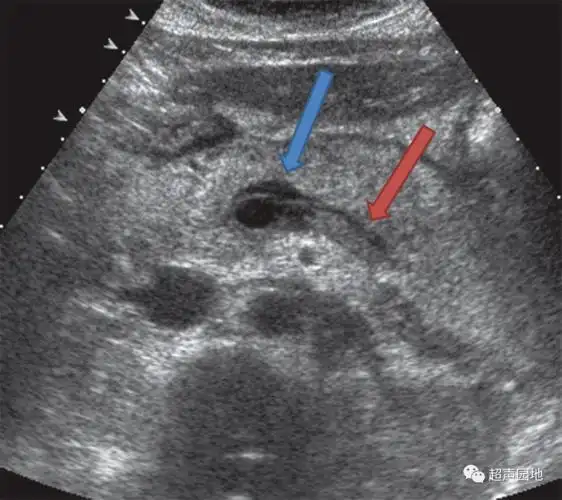

腹部超声脾

超基础这样的急性胰腺炎就离谱欢迎关注超声园地一起巩固超声基础知识